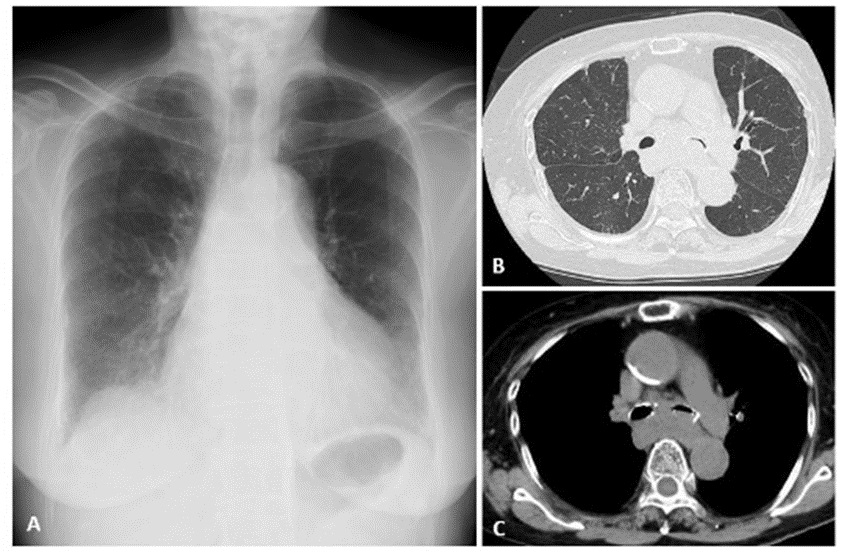

On November 5, auscultate the lung sounds of a patient with left bronchial obstruction. Use iPax to auscultate and compare the bronchial breath sounds on the left and right sides. (November 5, 2025)

11月5日は、左気管支閉塞のある症例の肺音です。左右の気管支呼吸音の違いを聴き比べてください。